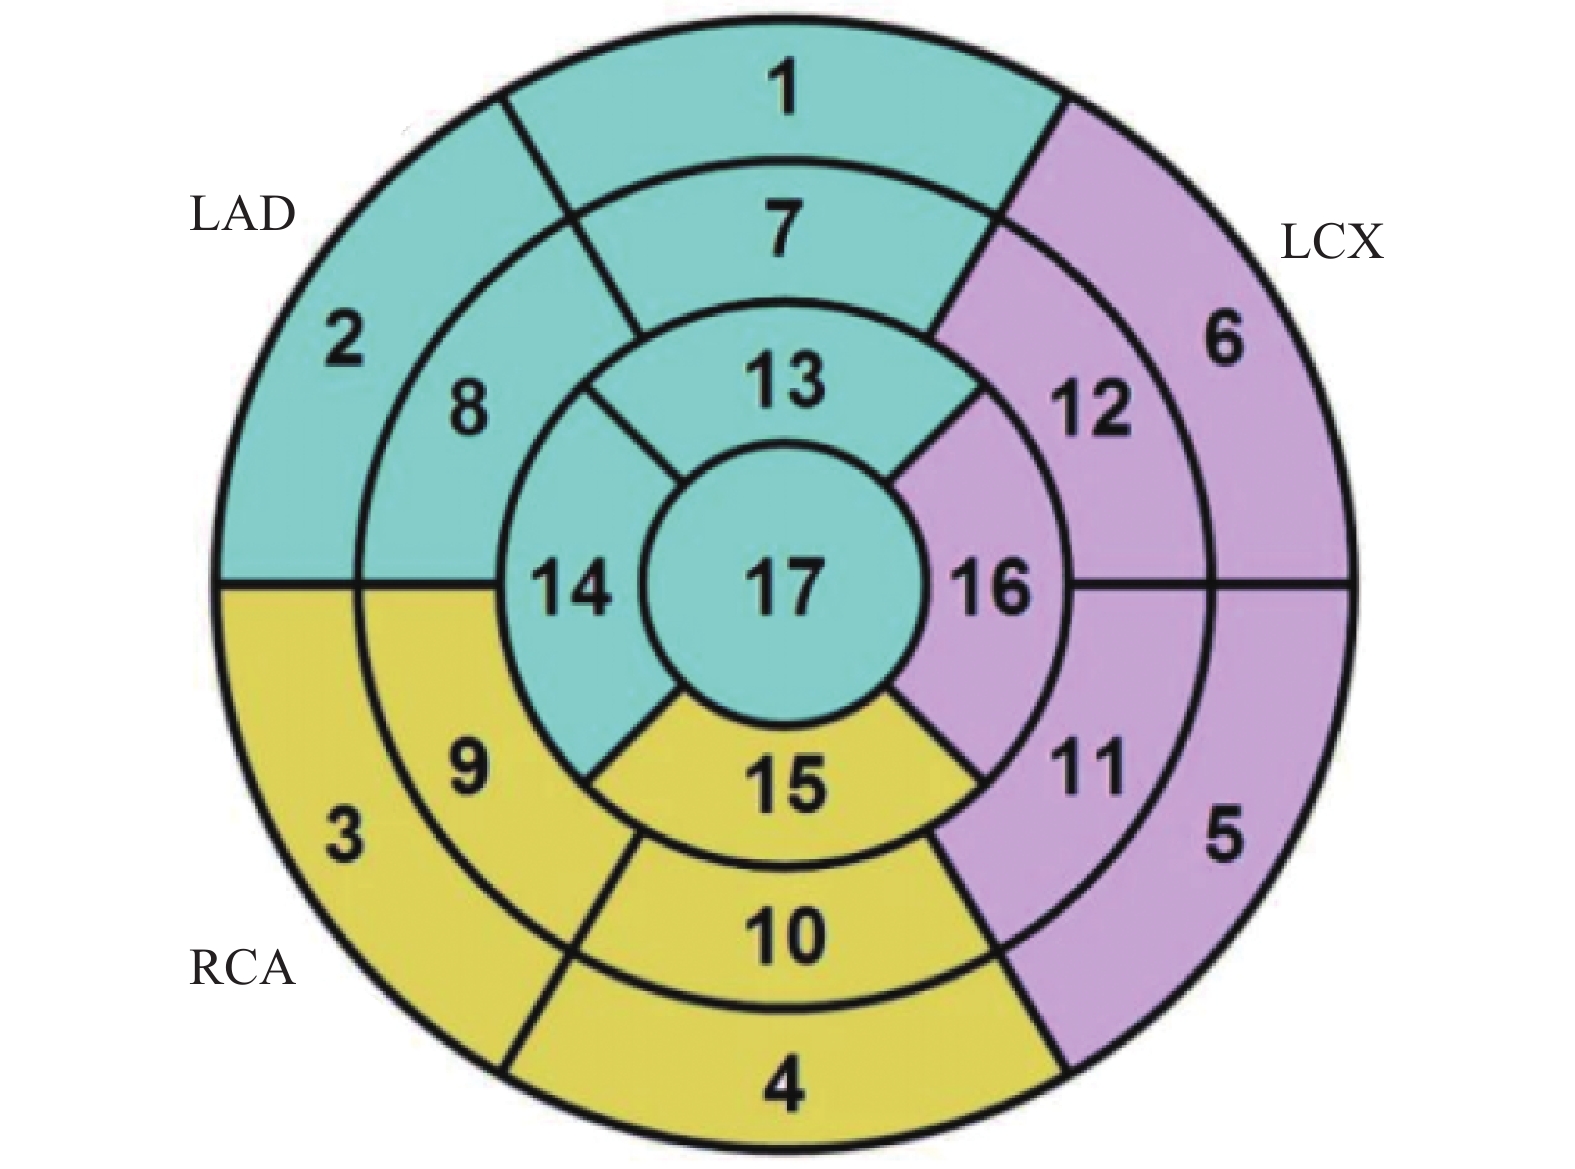

目的 通过心脏磁共振评估基于冠状动脉造影的微循环阻力指数对于冠状动脉微循环障碍的诊断效能,并进一步探究冠状动脉微循环障碍与无症状脑梗死间的相关性。 方法 选取2021年1月至2024年12月期间就诊于昆明医科大学第二附属医院心血管内科的患者231例。通过FlashAngio系统对冠状动脉造影图像左前降支血管进行分析得出caIMR值,以25为界限分为冠状动脉微循环正常组(caIMR<25,n = 126)和冠状动脉微循环障碍组(caIMR≥25,n = 105)。收集所有患者的一般临床资料、实验室指标(血常规、生化全套、糖化血红蛋白)、颅脑CT/MRI结果、心肌微循环磁共振灌注参数(达峰时间(tpeak)、相对峰值信号强度(RSIpeak)、最大上升斜率(Slopemax))、经胸超声心动图常规参数。 结果 (1)50例同时完善CMR和caIMR的患者, caIMR≥25组左前降支支配区域出现了不同程度的tpeak延长,RSIpeak和Slopemax降低,表明caIMR≥25组存在冠状动脉微循环障碍。进行Cohen's Kappa检验一致性分析, Kappa值0.839(P < 0.05),表明caIMR对于CMD的识别具有较高的准确度和评价效果;(2)127例糖尿病患者按照糖化血红蛋白(HbA1c)水平分为血糖控制良好组(4%≤HbA1c<6%)、血糖控制不佳组(6%≤HbA1c<8%)、血糖控制差组(HbA1c≥8%)。40例血糖控制良好组、59例血糖控制不佳组及28例血糖控制差组患者对比,血糖控制不佳组和血糖控制差组caIMR值中位数均高于血糖控制良好组(P < 0.05),且血糖控制不佳组caIMR中位数24.60接近于诊断冠状动脉微循环障碍的caIMR分界值25,血糖控制差组caIMR中位数32.15远高于分界值25;(3)在冠状动脉微循环障碍组中发现很多患者同时存在无症状脑梗死,而在冠状动脉微循环正常组患者中则较少,差异具有统计学意义(P < 0.05)。进一步进行Phi系数相关性分析,Phi系数0.562,差异具有统计学意义(P < 0.001)。提示冠状动脉微循环障碍与无症状脑梗死之间存在相关性。 结论 caIMR对于冠状动脉微循环功能障碍的识别具有较高准确度,且与心脏磁共振的评估效能一致性较高,而在冠状动脉微循环障碍的患者中发现大多同时存在无症状脑梗死,说明心脑微血管两者之间的病变发展可能存在相关性。 Abstract:Objective To evaluate the diagnostic efficacy of coronary angiography-based microcirculatory resistance index for coronary microcirculatory dysfunction through cardiac magnetic resonance (CMR), and further explore the correlation between coronary microcirculatory dysfunction and silent cerebral infarction. Methods 231 patients from the Cardiovasology Department of the Second Affiliated Hospital of Kunming Medical University between January 2021 and December 2024 were selected. The caIMR value of the left anterior descending coronary artery was analyzed using the FlashAngio system, with patients divided into normal coronary microcirculation group (caIMR<25, n = 126) and coronary microcirculatory dysfunction group (caIMR≥25, n = 105). General clinical data, laboratory indicators (complete blood count, biochemical panel, glycated hemoglobin), cranial CT/MRI results, cardiac microcirculatory perfusion MRI parameters (time to peak [tpeak], relative signal intensity at peak [RSIpeak], maximum upslope [Slopemax]), and routine transthoracic echocardiography parameters of all patients were collected. Results (1) Among 50 patients who completed both CMR and caIMR, the caIMR≥25 group showed varying degrees of tpeak prolongation, with reduced RSIpeak and Slopemax, indicating coronary microcirculatory dysfunction. Cohen's Kappa consistency analysis showed a Kappa value of 0.839 (P < 0.05), suggesting high accuracy of caIMR in identifying CMD; (2) 127 diabetic patients were categorized based on HbA1c levels into good glycemic control group (4%≤HbA1c<6%), moderate glycemic control group (6%≤HbA1c<8%), and poor glycemic control group (HbA1c≥8%). Comparing 40 patients in the good control group, 59 in the moderate control group, and 28 in the poor control group, the median caIMR values in the moderate and poor control groups were higher than the good control group (P < 0.05). The moderate control group's median caIMR of 24.60 was close to the diagnostic threshold of 25, while the poor control group's median caIMR of 32.15 was significantly higher; (3) In the coronary microcirculatory dysfunction group, several patients simultaneously had silent cerebral infarction, which was less common in the normal microcirculation group, with statistically significant difference (P < 0.05). Further Phi coefficient correlation analysis showed a coefficient of 0.562, with statistically significant difference (P < 0.001), suggesting a correlation between coronary microcirculatory dysfunction and silent cerebral infarction. Conclusion caIMR demonstrates high accuracy in identifying coronary microcirculatory dysfunction, with good consistency with CMR assessment. The high prevalence of silent cerebral infarction in patients with coronary microcirculatory dysfunction suggests potential interconnected pathological development in cerebral and cardiac microvascular systems. -

Table 9. Comparison of tpeak between the caIMR < 25 group and the caIMR ≥ 25 group[M(P25,P75)]

节段 caIMR<25组(n=24) caIMR≥25组(n=26) U/t P 1 20.50 (13.40,22.57) 36.35 (26.55,48.92) 124.000 <0.001* 2 15.30 (11.70,20.25) 31.00 (23.37,42.62) 81.500 <0.001* 7 21.65 (14.40,25.30) 34.95 (26.87,39.55) 4.438 <0.001* 8 22.00 (14.20,23.80) 35.05 (26.77,42.07) 103.500 <0.001* 13 19.50 (12.20,27.70) 29.90 (25.47,38.45) 155.000 0.001* 14 20.75 (12.50,29.55) 34.20 (25.02,42.17) 3.955 <0.001* *P < 0.05。 表 10 caIMR<25组与caIMR≥25组RSIpeak比较[M(P25,P75)]

Table 10. Comparison of RSIpeak between the caIMR < 25 group and the caIMR ≥ 25 group[M(P25,P75)]

节段 caIMR<25组(n=24) caIMR≥25组(n=26) U P 1 163.250 (106.525, 1099.375 )110.900 (90.225,136.425) 243.000 <0.001* 2 160.800 (123.600,232.725) 144.300 (106.750,997.725) 342.000 0.004* 7 182.700 (125.825, 1188.825 )125.550 (117.900,164.150) 259.500 <0.001* 8 142.000 (137.000,166.000) 159.600 (119.825, 1173.275 )287.000 0.253 13 207.250 (148.675, 1274.100 )189.700 (173.050,251.600) 310.000 0.001* 14 193.250 (164.475,221.300) 204.800 (149.125, 1187.375 )304.000 0.641 *P < 0.05。 表 11 caIMR<25组与caIMR≥25组Slopemax比较[M(P25,P75)]

Table 11. Comparison of slopemax between the caIMR < 25 group and the caIMR ≥ 25 group [M(P25,P75)]

节段 caIMR<25组(n=24) caIMR≥25组(n=26) U P 1 12.500 (8.000,68.775) 10.100 (6.700,12.100) 284.500 <0.001* 2 16.950 (9.800,30.275) 13.950 (8.650,63.550) 340.500 <0.001* 7 12.200 (9.825,14.750) 12.400 (8.650,64.350) 315.500 0.326 8 14.700 (11.325,16.100) 12.500 (8.775,59.350) 323.000 <0.001* 13 18.500 (13.975,36.400) 15.450 (10.850,91.625) 346.500 0.003* 14 17.900 (11.050,22.700) 16.900 (11.075,68.200) 316.500 0.001* *P < 0.05。 表 12 caIMR组与CMR组交叉表分析